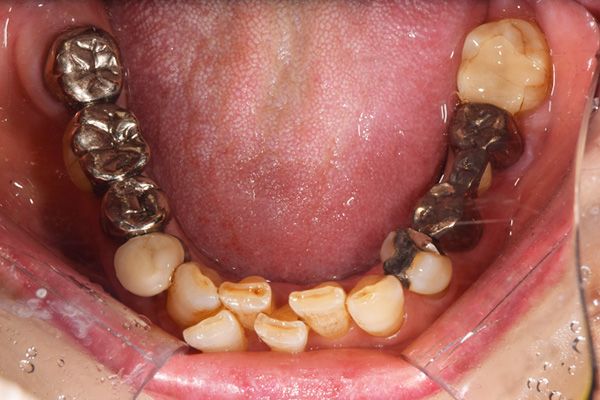

前歯が折れて当院にいらっしゃいました。 過去に下の入れ歯を作ったが、合わなくなってずっと入れ歯をいれていらっしゃらない患者様でした。 これは奥歯で噛むことができないため、前歯で噛むことを繰り返したために、負担に耐えられなくなった前歯が折れてかぶせ物ごと 外れてしまったのだと考えられます。 痛くない、違和感の少ない、下の入れ歯を作ることがこの方のゴールであると考えられました。

上下の入れ歯が外れやすくなったということでいらっしゃいました。 顎の骨はしっかりしていましたので、精密な型取りさえすればしっかりした入れ歯がつくれると思いました。 また下には6本歯が残っていましたが、虫歯になっている歯もありました。 かぶせ物のなかで大きな虫歯があった歯があり、1本だけ残せない状態でした。

上の入れ歯は確かに吸着は甘くなっていました。 また下の入れ歯はバネの一部が壊れており、安定感がなくなっていました。